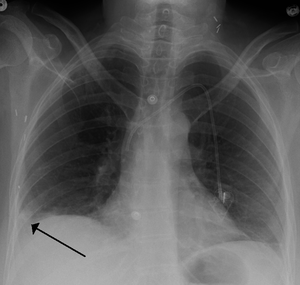

يتم من خلال الأعراض المذكورة آنفاً وعن طريق الفحوصات الشعاعية كصورة الصدر الشعاعية, والتصوير الطبقي المحوري أو من خلال الصور النووية للرئتين، والفحوصات المخبرية الأخرى التي تساعد في التشخيص تعداد الدم الكامل وسرعة تجلط الدم، كما تجرى بعض التحاليل الدموية كإجراء وقائي ومنها فحص وظائف الكبد والكلى ومعدلات الشوارد وسرعة تسفل الدم. ومسح التهوية والتروية الرئوي هو شكل من التصوير الشعاعي التشخيصي هدفه تقييم التروية والتهوية في الرئتين ويستخدم في تشخيص الانصمام الرئوي. التصوير فوق الصوتي أو التخطيط التصواتي لأوعية الساق الدموية مهم لتقييم وجود أي خثار في أوردة الساق، يعد الإثبات بالإصابة بالخثار الوريدي العميق / جلطة الساق دليلاً هاماً على القابلية العالية للإصابة بالانصمام الرئوي. تخطيط القلب الكهربائي هو إجراء روتيني لأي مريض يأتي بألم في الصدر ويستخدم لإثبات أو نفي وجود احتشاء العضلة القلبية أو الذبحة الصدرية، كما لوحظ وجود 3 علامات كلاسيكية على تخطيط القلب الكهربائي في حالات الانصمام الرئوي وهي: موجة S كبيرة على القطب الأول I موجة Q كبيرة على القطب الثالث III موجة T معكوسة على القطب الثالث III ,7-8 ,3-5.[16]

أفضل تصوير شعاعي متاح لتشخيص الانصمام الرئوي هو تخطيط الأوعية الدموية في الرئة، ولكن نظرً لكون هذا الإجراء باضعاً (Invasive) وينطوي على بعض المضاعفات الجانبية فإن استخدامه يبقى محدوداً.

التصوير الطبقي المحوسب

التصوير الطبقي المحوسب للرئة والمصحوب باستخدام الصبغة المشعة في الوريد أصبح واسع الانتشار والاستخدام في تشخيص المرضى المشتبه بإصابتهم بالانصمام الرئوي، لهذا النوع من التصوير حساسية تبلغ 83% ودقة نوعية تصل إلى 96%.[24].[25]